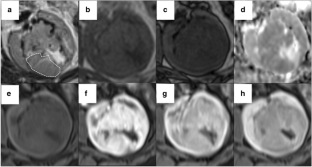

Fig. 1